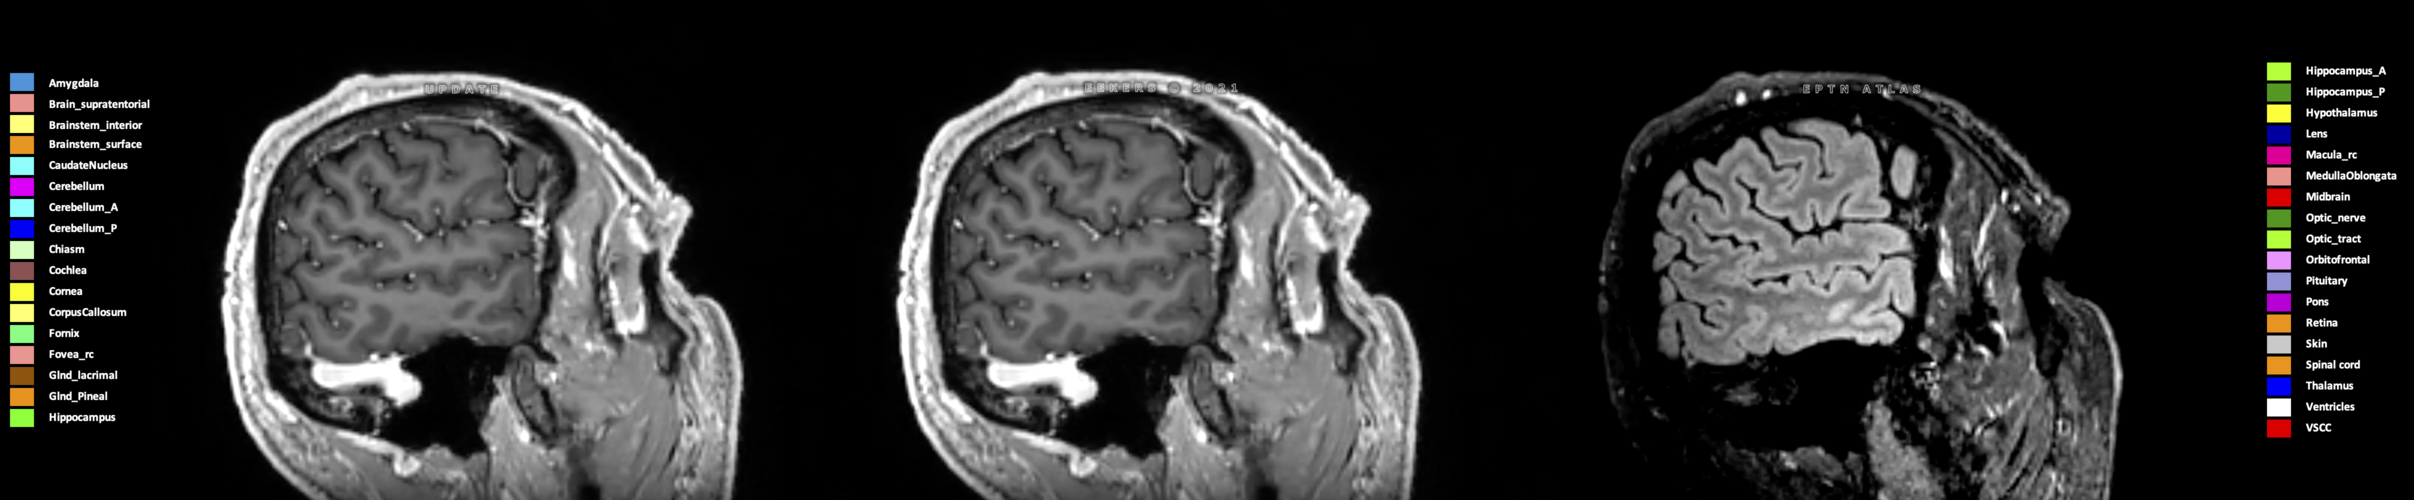

Three-dimensional delineation of the 25 consensus OARs for neuro-oncology are shown on CT (WW/WL 120/40, 3000/600), 3T MR images, (T1Gd, T2FLAIR 1mm) and 7T MR (MP2RAGE 0.7 mm). All are presented in transversal, sagittal and coronal view.